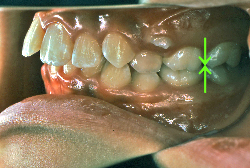

「ものがうまく噛めない」という主訴で来院したケースです。診断の結果、「骨格性反対咬合に伴う咬合不良+軽度叢生」と判明しました。原因としては特に下顎の左側が過成長したため、骨格性反対咬合になり、特に左側での噛み合わせが非常に悪くなっていると診断しました。初診時の写真を見ると、上下の正中線の大きなズレ、左側の噛み合わせの不良がはっきり分かります(黄色の矢印と緑の矢印は一致しているのが正しい状態です)。